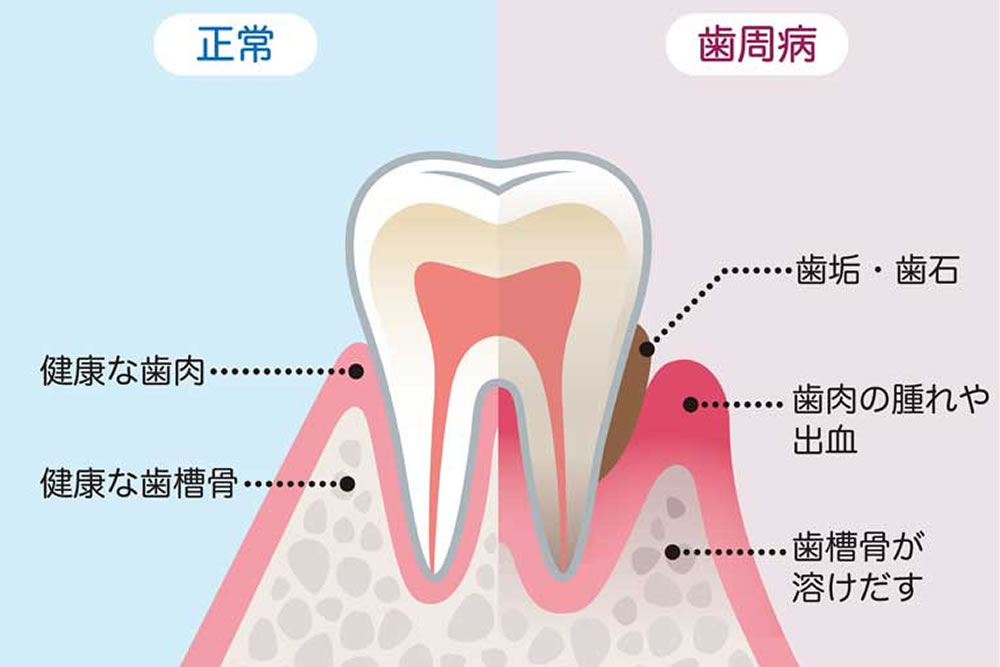

歯周病とは?

歯周病は、細菌の感染によって生じる炎症性の歯科疾患です。

毎日の歯磨きがきちんと行われていないと、歯と歯茎のすき間に汚れがたまり、細菌が増殖します。その影響で歯茎に炎症が生じ、出血や腫れがみられるようになります。

さらに進行すると、歯を支えている骨(歯槽骨)が溶け、歯がぐらつき、最終的には抜けてしまうこともあります。

歯周病治療における最大の敵である細菌は、主に固まりとなって歯石という形で認識できるようになります。この歯石が歯と歯ぐきの間(歯周ポケット)に挟まって炎症を起こし、歯肉や歯槽骨を溶かすのが歯周病です。

歯周病治療における最大の敵である細菌は、主に固まりとなって歯石という形で認識できるようになります。この歯石が歯と歯ぐきの間(歯周ポケット)に挟まって炎症を起こし、歯肉や歯槽骨を溶かすのが歯周病です。

歯周ポケットの奥深く7~8mmまで付着した歯石はもはや肉眼では把握できず、除去することはおろか、気づくことすらできません。